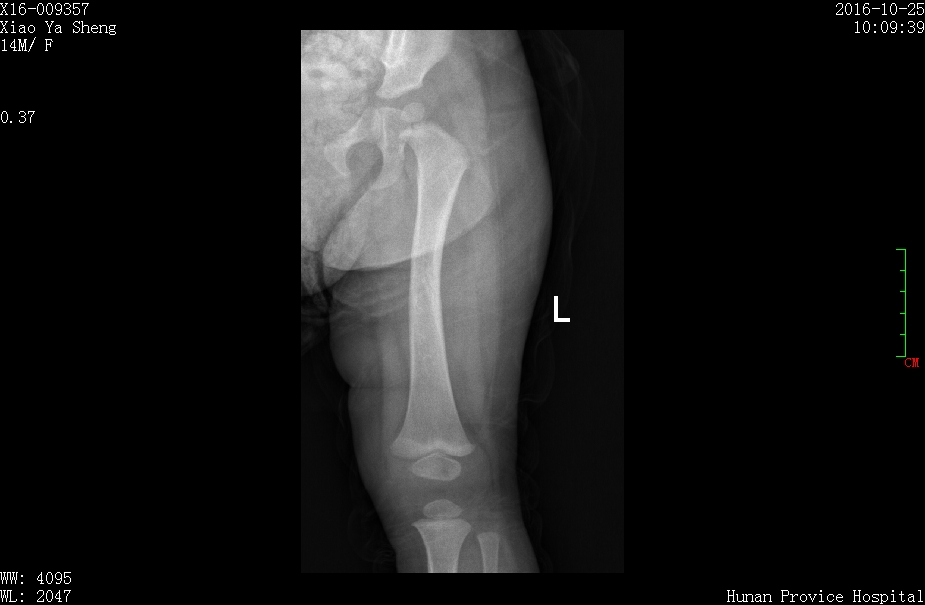

3月女婴股骨骨折正位片

3月女婴股骨骨折侧位片

2 月后复查正位片

2月后复查侧位片

1年后复查正位片,已完全愈合,自行矫形至正常